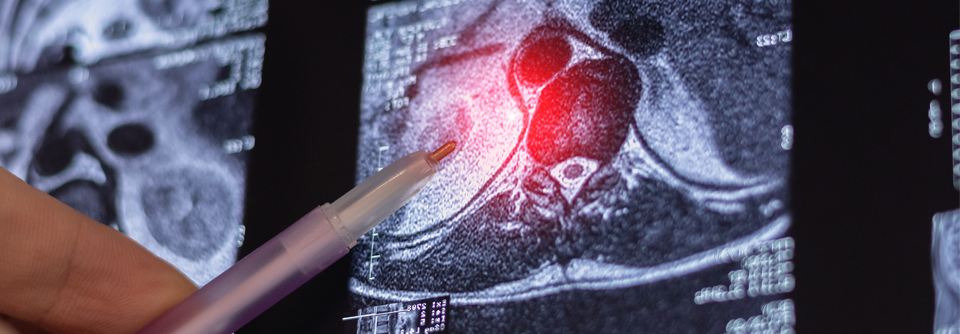

Durch KI-Algorithmen und die Diffusions-Tensor-Bildgebung (DT-MRT) ist die Diagnose einer Autismus-Spektrums-Störung womöglich schon vor dem Alter von zwei Jahren möglich. Durch KI-Algorithmen und die Diffusions-Tensor-Bildgebung (DT-MRT) ist die Diagnose einer Autismus-Spektrums-Störung womöglich schon vor dem Alter von zwei Jahren möglich. © shidlovski – stock.adobe.com

Mit Hilfe von KI-Algorithmen und der Diffusions-Tensor-Bildgebung (DT-MRT) lässt sich die Diagnose einer Autismus-Spektrum-Störung womöglich bald früher stellen, berichtete Mohamed Khudri von der Universität Louisville. Anhand der DT-MRT kann man die Konnektivität des Gehirns darstellen. Eine Störung der Verbindungen zwischen den Hirnregionen gilt als eine primäre Ursache für Autismus. Der Algorithmus wurde darauf trainiert, Unterschiede in der Konnektivität aufzudecken.